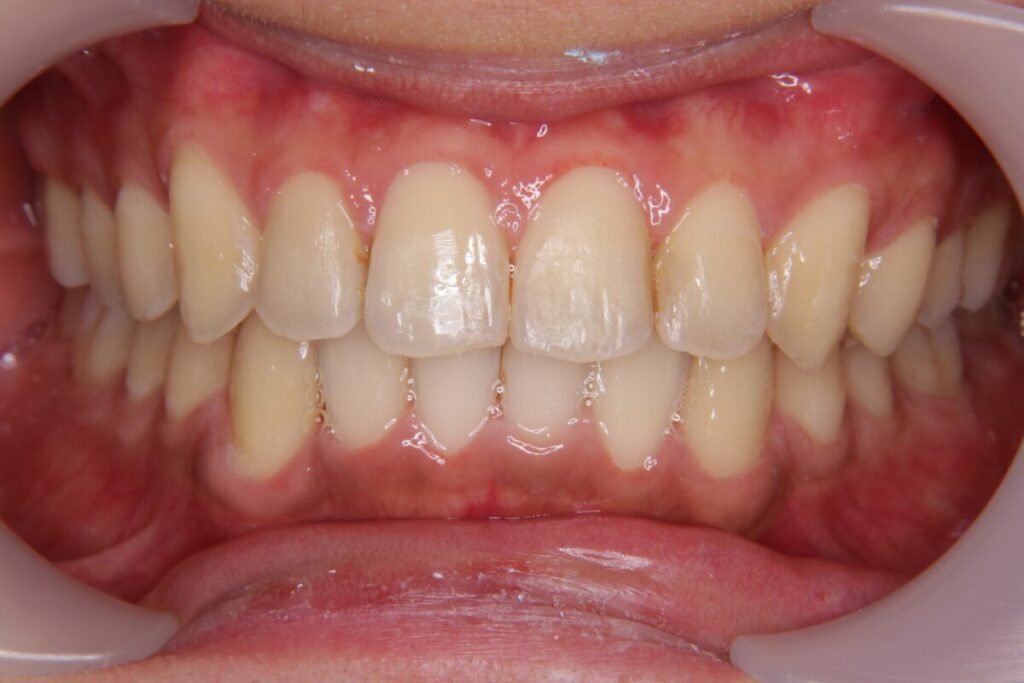

| 患者 | 28歳男性 |

|---|---|

| 主訴 | 歯ならびのガタガタ |

| 診断名 | UR7/LR7クロスバイトと上下叢生を伴うAngleⅠ級sk.1不正咬合 |

| 治療内容 | マウスピース型矯正装置(インビザライン)、部分的に上顎前歯部にワイヤー併用 |

| 抜歯の有無 | 非抜歯 |

| 治療期間 | 2年 |

| 費用(税込) | 594,000円 |

| リスクと副作用 | 痛み等、歯根吸収/歯肉退縮、後戻り、むし歯・歯肉炎の可能性。 |

【医師コメント】

上下のガタつきで来院された患者さんです。

精密検査の結果、UR7/LR7のクロスバイト(交叉咬合)と上下の叢生を伴う AngleⅠ級(sk.1)不正咬合 と診断しました。奥歯の前後関係はⅠ級で大きなズレは強くない一方、奥歯の噛み合わせのズレとスペース不足が原因でした。

治療はインビザラインを主体に非抜歯で計画し、歯列全体のバランスとかみ合わせの安定を意識しながら段階的に改善を進めました。

終盤、UL2のローテーションがわずかに残ったため、仕上げの精度を高める目的で上顎前歯部に部分的にワイヤーを併用しています。

治療は計画に沿って進行し、2年で歯列の配列とかみ合わせの改善を図ることができました。